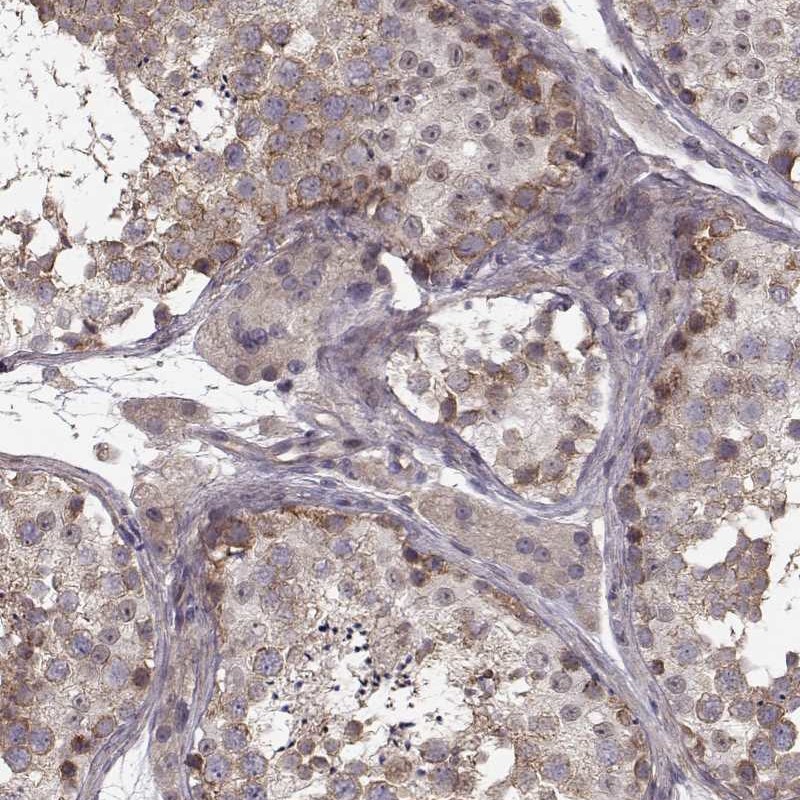

Immunohistochemical staining of human testis shows strong cytoplasmic positivity in cells in seminiferous ducts.